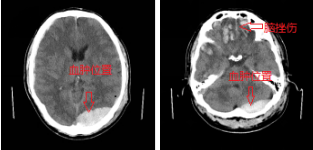

2021年01月15日,突如其来的意外打破了患者桑某一家的平静生活,39岁的患者桑某不慎从3米高的楼上摔下,当即昏迷,家属立即送患者至阿坝州人民医院神经外科住院治疗,由值班医生详细询问病史和全面查体后诊断为“重型闭合性颅脑损伤:1.左侧枕部小脑骑跨性硬膜外血肿;2.双侧额叶脑挫裂伤。由于患者颅内出血量较大,随时可能病情加重甚至危机生命,介于患者颅内多出损伤,且相当严重,值班医生立即上报了文家智副主任医师,文医生得知患者病情后第一时间赶到科室,进一步掌握患者病情后,建议患者需要立即行手术治疗,家属焦急万分,一时拿不定主意,主管医生耐心与患者家属沟通解释病情,并分析手术利弊,逐步取得了家属信任,决定接受医生建议同意手术。

由于血肿位置特殊,手术区域临近重要血管,如若损伤可能危机生命,较普通手术有一定难度。由于术前手术医师的充分准备和术中对重要血管的保护,经过五个小时的手术治疗,手术顺利成功完成,患者术后转入了医院重症监护室进一步监护治疗。术后复查颅脑CT发现,患者原本双侧额叶的脑挫伤出血增多,为保证患者生命安全和避免多次手术及巨额治疗费用,经科室讨论,放弃以往的“骨瓣减压术”手术方式而选择了现国内外推荐可行的“颅内压监测/脑室外引流术”,该手术技术在神经外科已成熟并已经成功救治多例患者。主管医生再次向家属详细 病情及下一步治疗方案并同时了解到患者家庭经济困难,于是安抚患者家属的同时宣传阿坝州医保政策,包括大病医疗补助,水滴筹多种方式来解决经济困难以救治患者,患者家属焦虑的心情得以平复,经过商议和医生们的充分准备,患者顺利进行了第二次手术治疗。